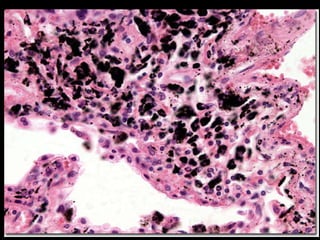

Pigmentos Exógenos Pneumoconioses Carvão (antracose) Sílica (silicose) Asbestos (asbestose) Outras: Tatuagem

Pigmentos Exógenos PneumoconiosesCarvão (antracose) Sílica (silicose) Asbestos (asbestose) Outras: Tatuagem